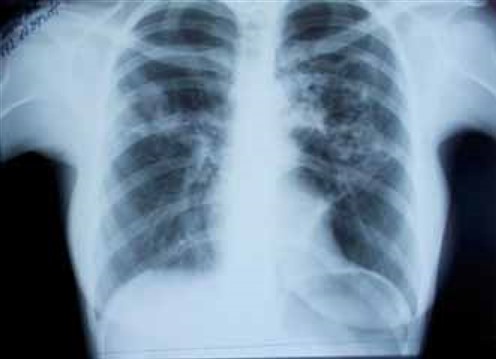

На контрольной обзорной РГ ОГК в прямой проекции от 09.10.15 (на 15-й день лечения в стационаре) определяется положительная рентгенологическая динамика (рис. 3):

cлева и справа в верхних и средних отделах уменьшились размеры и интенсивность участков инфильтрации легочной ткани. Заключение: двусторонняя верхнедолевая пневмония в стадии разрешения. (О.В.Фатенков с соавт., 2018)

Учитывая замедленную и слабовыраженную положительную динамику с учетом длительной комбинированной антибактериальной терапии, рекомендовано проведение компьютерной томографии (КТ). КТ выполнена 10.10.15 (рис. 4).

На серии снимков КТ ОГК, выполненных в специальной программе, слева в S6 определяется крупное полостное образование с толстыми стенками и перегородками в структуре размером 80 × 55 мм с многочисленными перифокальными разнокалиберными очагами, зоной снижения прозрачности по типу консолидации (инфильтрации). Слева в верхней и нижней долях – крупные центрилобулярные воздушные полости размером ≤ 33 мм (центрилобулярная эмфизема). Также слева отмечается фиброателектаз S3 с цилиндрическими бронхоэктазами. Справа в S3 верхней доли и S5 средней доли определяются многочисленные очаги ≤ 8 мм с тенденцией к слиянию. Легочный рисунок не усилен. Просвет трахеи, бронхов среднего калибра сохранен, стенки бронхов не утолщены. Лимфатические узлы правой паратрахеальной группы умеренно увеличены (≤ 15 мм по линии оси). Сердце, магистральные сосуды и диафрагма обычно расположены, контуры их не изменены. Жидкость в плевральных полостях не визуализируется. (О.В. Фатенков с соавт., 2018)

По данным КТ – картина инфильтративного ТЛ с распадом. Учитывая выраженные сохраняющиеся изменения после проведенного лечения, наличие полостей распада, характерные для ТЛ, пациентка повторно направлена в специализированное учреждение – противотуберкулезный диспансер. При обследовании фтизиатром диагноз ТЛ подтвердился, обнаружены МБТ методом микроскопии, пациентка переведена на дальнейшее лечение в противотуберкулезный диспансер. (О.В. Фатенков с соавт., 2018)